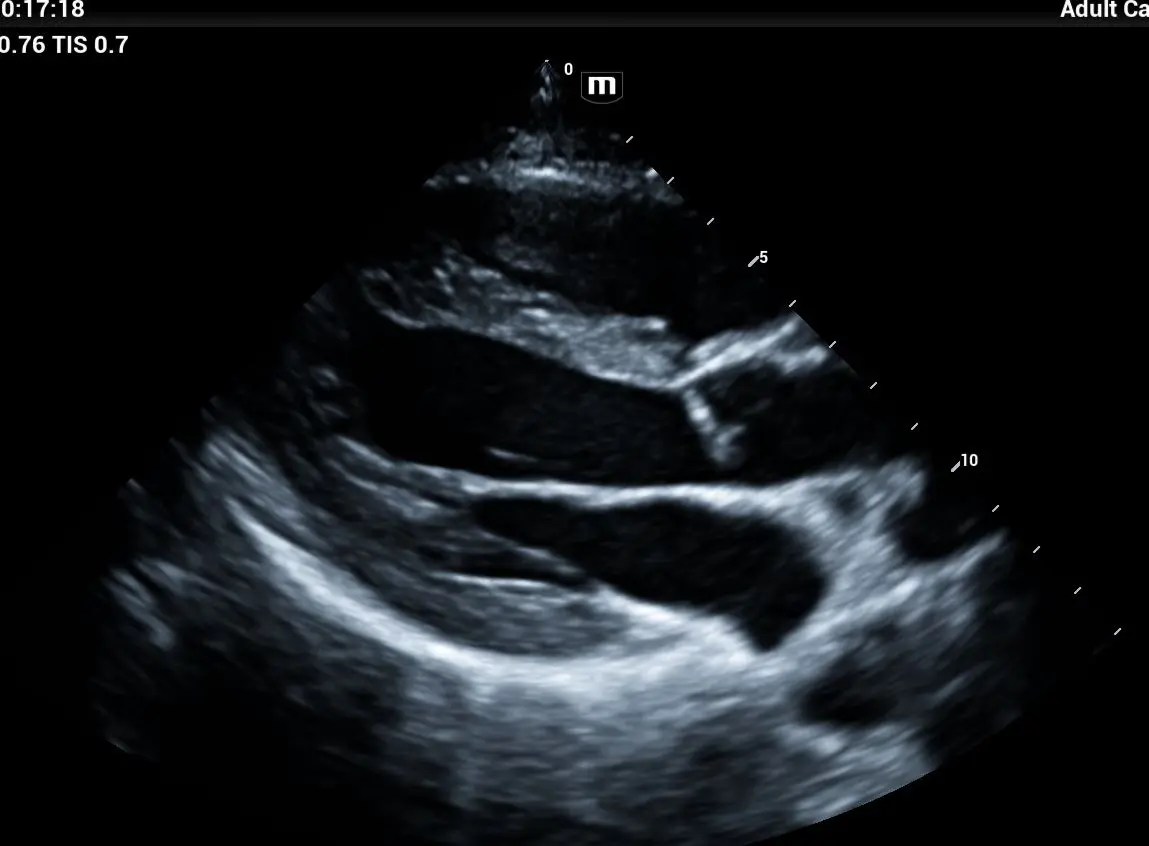

Ecocardiograma Doppler Color Transtorácico y Strain Longitudinal

Incluye perfil de lípidos 11 elementos.

Evalúa cavidades, válvulas, flujo y fuerza de contracción. Dirigido a pacientes con presión alta, dolor torácico, arritmias o revisión preventiva.

¿Qué es el Ecocardiograma ?

El ecocardiograma es un estudio de imagen cardíaca que utiliza ultrasonido para obtener imágenes en tiempo real del corazón. Es una de las principales herramientas diagnósticas en cardiología porque no es invasivo, determina cardiopatías, insuficiencia cardiaca , el flujo sanguíneo , enmerdades valvulares.

¿Qué es el Ecocardiograma Doppler con Strain?

Es una evaluación cardiovascular de alta precisión que permite analizar el funcionamiento estructural y mecánico del corazón en tiempo real, midiendo no solo la anatomía, sino también la contractilidad y deformación miocárdica (Strain). Con la tecnología Philips Affinity 70, LIB Laboratorios ofrece un estudio de nivel hospitalario, ideal para la detección temprana de enfermedades cardíacas (insuficiencia, Valvulopatías, Fibrosis, Isquemias, Amiloidosis…) y el seguimiento de tratamientos farmacológicos (Cardiotoxicidad).